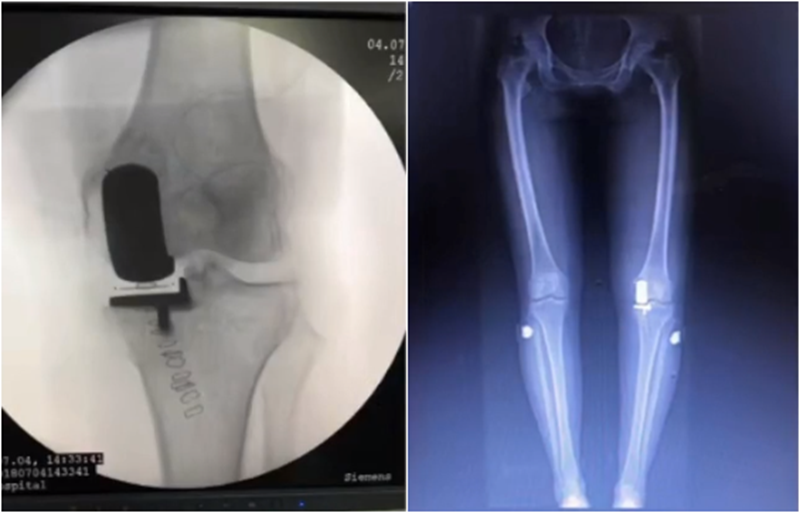

牛津单髁课程表明,单髁只纠正关节内畸形,恢复下肢得病前的力线,不纠正关节外畸形。

但实际术后需要通过全长片来判断是否能取得好的力线,判断有无过度矫正或矫正不足的情况出现。还需要通过全长片区分内翻畸形的来源在哪里,是否能矫正,对适应证的选择有一定帮助。如果术后下肢整体力线外翻3°,则说明外侧间室压力明显升高。

小结:对于下肢整体力线,首先保证术后力线不能外翻,术后力线内翻不能超过10°,而术前关节外畸形不能超过10°。

除了下肢整体力线,还要考虑假体位置。理想状态下,假体位置对位好,力线轻度内翻。